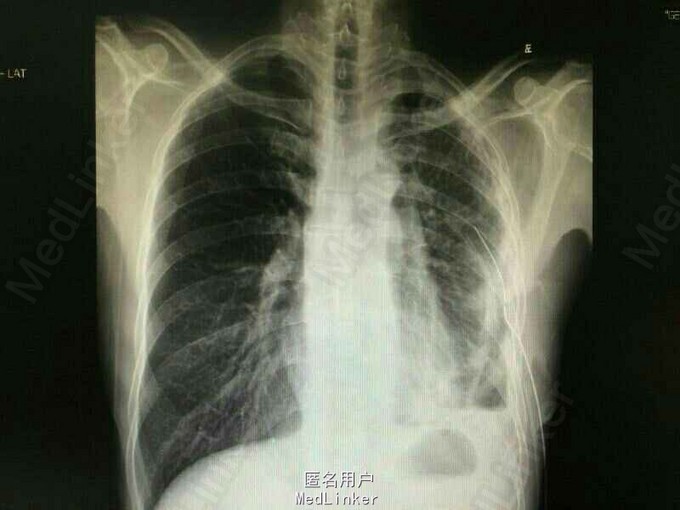

病史及辅助检查提示肺癌,但无病理标本;持续液气胸,故拟行“胸腔镜下左侧胸腔探查+肺楔形切除+胸膜活检术”。右侧卧位,三孔进胸,见胸膜广泛增厚,呈皮革样,取壁层胸膜及肺结节活检。术后予对症补液及抗感染处理,患者生命体征平稳。 术后复查胸片:左肺术后,左肺渗出,较前吸收。 术后病理:(左下肺组织)肺浸润性腺癌,II级,腺泡状生长方式。 (胸水)涂片发现癌细胞,为腺癌。 (胸膜组织)见腺癌浸润。